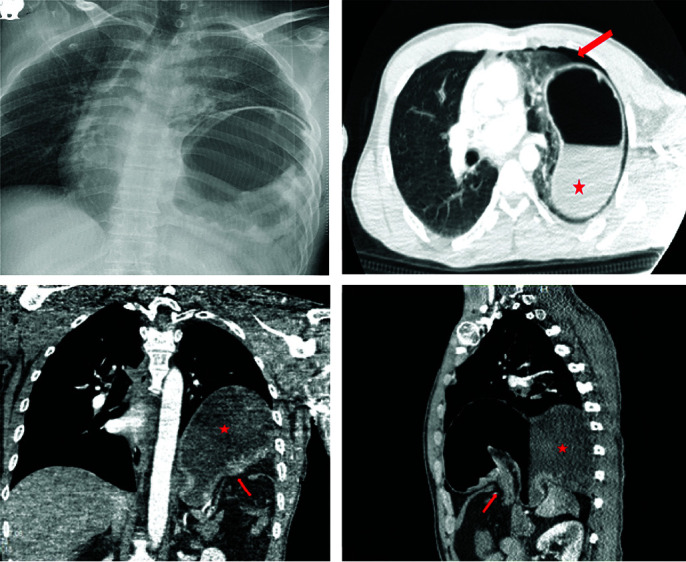

Case presentation: We report the case of a 39-year-old male patient who sustained blunt thoracoabdominal trauma in a motor vehicle accident. The patient presented with respiratory distress and generalized abdominal tenderness. Imaging revealed a left diaphragmatic defect with herniation of abdominal organs into the thoracic cavity.

Surgical technique: The patient underwent diagnostic laparoscopy, which confirmed an 8 × 5 cm defect in the left diaphragmatic dome with herniation of the stomach and omentum. The herniated organs were reduced, and the defect was repaired tension-free using intracorporeal 0-silk sutures. A 28-Fr intercostal drainage tube and a 12-Fr abdominal drain were placed.

Outcome: The postoperative course was uneventful. A chest x-ray on postoperative day one confirmed normal diaphragm position and re-expansion of the lung. The patient recovered without complications.